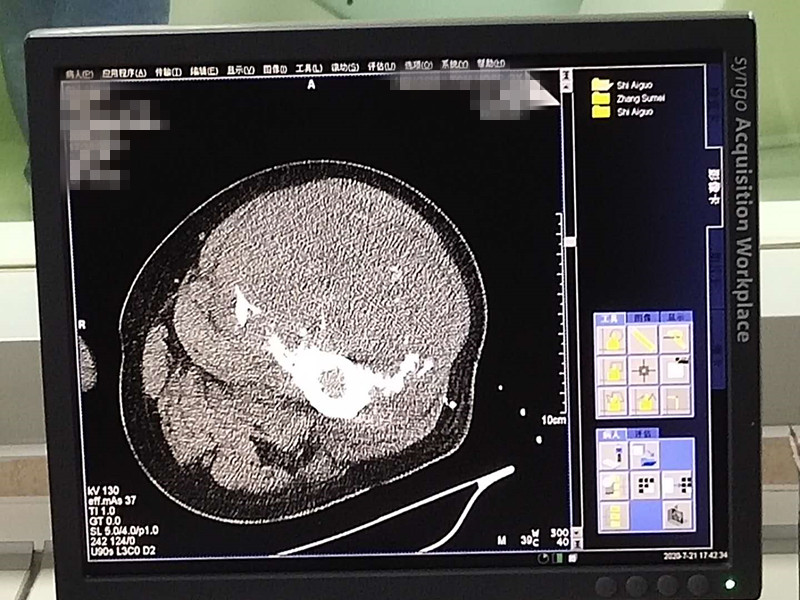

75岁腿部软组织肉瘤氩氦刀冷冻消融